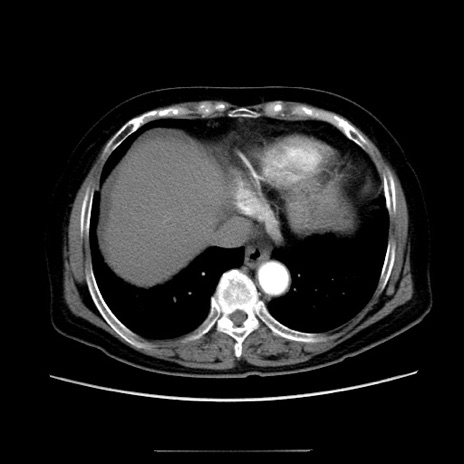

症例5(横断像)

冠状断像

【症例】70歳代女性

【主訴】お腹が張る

【現病歴】1週間くらい前から腹部膨満の自覚あり。昨日夜から増悪したため、本日救急外来受診。

【身体所見】意識清明、BT 36.5℃、BP 165/106mmHg、HR 80bpm、SpO2 98%、腹部:膨満、軟、自発痛・圧痛なし、触診にて不快感あり、腸蠕動音:減弱

【データ】WBC 12600、CRP 1.04